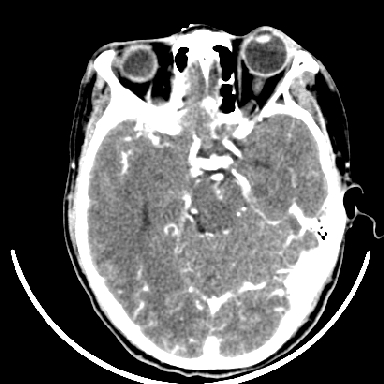

标题: CT6056:脑出血(血管畸形?) [打印本页]

标题: CT6056:脑出血(血管畸形?)

m 40突发头痛左侧偏瘫3小时

考虑高血压性脑出血,依据:

1是高血压性脑出血的好发部位,形态呈肾形,是高血压性脑出血的常见形状

2增强时占位效应加重了,考虑出血还没有停止

3病灶周围水肿不是太厉害,一般肿瘤出血水肿多非常明显

4病灶周围的‘软组织’影没有明显的强化

5至于脑血管畸形引起的出血,暂时没有看到明显的畸形血管影,也不太支持

支持右侧基底节脑出血

右侧基底节区脑出血.

支持右侧基底节区(主要为外囊区)原发性脑出血。

另附部分资料:“血液溢出血管外形成血肿,其内含有大量血红蛋白、血浆白蛋白,球蛋白,因这些蛋白对x线的吸收系数高于脑质,故ct呈现高密度阴影,ct值达40~90h,最初高密度灶呈非均匀一致性,中心密度更高,新鲜出血灶边缘不清。基底节区血肿多为“肾”型,内侧凹陷,外侧膨隆,因外侧裂阻力较小,故向外凸,其它部位血肿多呈尖圆形或不规则形”

术中抽出40ml陈旧血液,血肿底部似见一条索血管影